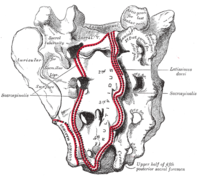

في البشر، العجز sacrum ( []ˈsækrəm[] أو []ˈseɪkrəm[]; مفرده: sacrums أو sacra)، هي عظام كبيرة، مثلثة الشكل، تقع على قاعدة العمود الفقري وعلى الجزء العلوي، الخلفي لتجويف الحوض، حيث تكون مغروزة مثل الوتد بين عظام الورك. الجزء العلوي منها تتصل بالفقرة القطنية، والجزء السفلي منها متصلة بالعصعص. عادة، يبدأ العجز كفقرة خامسة غير ملتحمة تبدأ بالالتحام في عمر 16-18 سنة وعادة ما يكتمل التحامها كعظمة واحدة في الرابعة والثلاثين.